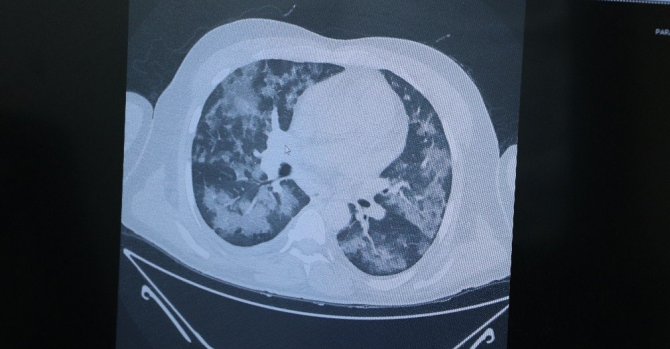

Tedavi altındaki 5 kişinin akciğerlerini inceleyen Prof. Dr. Özkaya, "Hâlâ bu hastalığa inanmayanlar olabilir. Bu hastalığın yapay, suni bir medya haberi olduğu söyleniyor. Size şu an 5 hasta örneği göstereceğim. 5'i de şu an yatıyor ve yaşam mücadelesi veriyor. Okulda bir yarışma düzenlendiğini düşünün, tüm Türkiye'de okullar arası bir yarışma yapılıyor ve yarışmada bir resim yapmanızı istiyorlar. Tüm Türkiye'deki bütün okullardaki öğrenciler birbirinden bağımsız olarak aynı resmi yapıp getiriyorlar. Böyle bir şey mümkün mü? 58 yaşında bir hastamız, akciğerinde yaygın Covid-19 lekesi. Birbirinden bağımsız ayrı insanlar. Yine aynı tabloyla gelen başka bir hasta ve yine aynı tabloyla yatan başka bir hasta. Bu hastaların hepsi şu an yaşam mücadelesi veriyor ve büyük oranda tedavi edebildiğimiz hasta grupları. Böyle bir tabloyu biz bugüne kadar hiç görmedik. Bugüne kadar yaşayan en yaşlı doktorlar bile akciğerleri böyle etkileyen bir bulaş hastalığı görmedi. Bu bir gerçektir, bu bir yaşadığımız hayat tecrübesidir. Lütfen daha duyarlı olalım" ifadelerini kullandı.